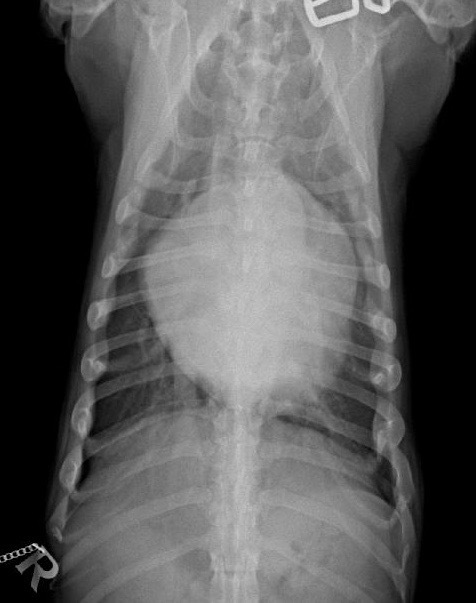

Durch die Herzultraschalluntersuchung konnte dann leider der Verdacht auf eine deutlich weiter fortgeschrittene Herzerkrankung bestätigt werden. Neben einer hochgradigen Vergrößerung der linken Herzhälfte durch die Klappeninsuffizienz ließ sich außerdem ein moderat erhöhter Druck in den Lungenarterien feststellen. Dies nennt man Pulmonale Hypertension oder Lungenhochdruck. Für eine solche Erhöhung des Blutdruckes im Lungenkreislauf gibt es unterschiedliche Ursachen. Eine davon ist ein bestehendes Lungenödem durch ein Linksherzversagen, wie es bei Alf nun offensichtlich der Fall war. Da die Diagnose nun „dekompensierte Mitralklappenendokardiose“ - oder nach der CHIEF - Klassifizierung Stadium C2 * - lautete, verordnete ich dem kleinen Hund zusätzlich zwei weitere Medikamente zur dauerhaften Herztherapie (eines zur Entwässerung und das andere zur Entlastung des Herzens durch Weitstellung der Arterien und zur Unterstützung der Pumpfunktion des Herzmuskels). Die am Morgen im Wald aufgetretene „Synkope“ ließ sich also eindeutig durch die fortgeschritten Herzerkrankung erklären.

Drei Tage später wurde Alf noch zur Röntgenuntersuchung einbestellt, um den Erfolg des Entwässerungsmittels zu überprüfen. Er machte laut Besitzerin einen deutlich muntereren Eindruck und sein Appetit war unter der neuen Herztherapie wieder normal geworden. Die zu Hause ermittelte Ruhe-Atemfrequenz lag bei 22 Atemzügen pro Minute. Da radiologisch aber weiterhin ein leichtes Lungenödem zu erkennen war, wurde die Dosis der „Entwässerungstabletten“ noch etwas erhöht. Zur nächsten Herz-Ultraschall-Kontrolle wurde der Dackel drei Monate später vorgestellt. Er hatte etwas an Gewicht zugelegt, war laut Besitzerin immer „gut drauf“, zeigte durchgehend eine normale Atmung und hatte keine weitere Synkope. Die Befunde am Herzen waren stabil, nur wurde im mitlaufenden EKG nun eine zusätzliche Herzrhythmusstörung festgestellt, sogenannte Vorhof-Extrasystolen. Die Herztherapie wurde daher um ein antiarrhythmisch wirkendes Medikament ergänzt. Unter dieser Therapie verlebte Dackel Alf einen fröhlichen Sommer inklusive Dänemarkurlaub. Da zwischendurch die Ruhe-Atemfrequenz ein wenig angestiegen war, wurde die Dosis der „Entwässerungstabletten“ noch etwas erhöht. Bis zur nächsten kardiologischen Kontrolle weitere sechs Monate später lag diese dann immer im normalen Bereich zwischen 16 und 20 Atemzügen pro Minute und auch die Ultraschallbefunde waren weiterhin stabil.